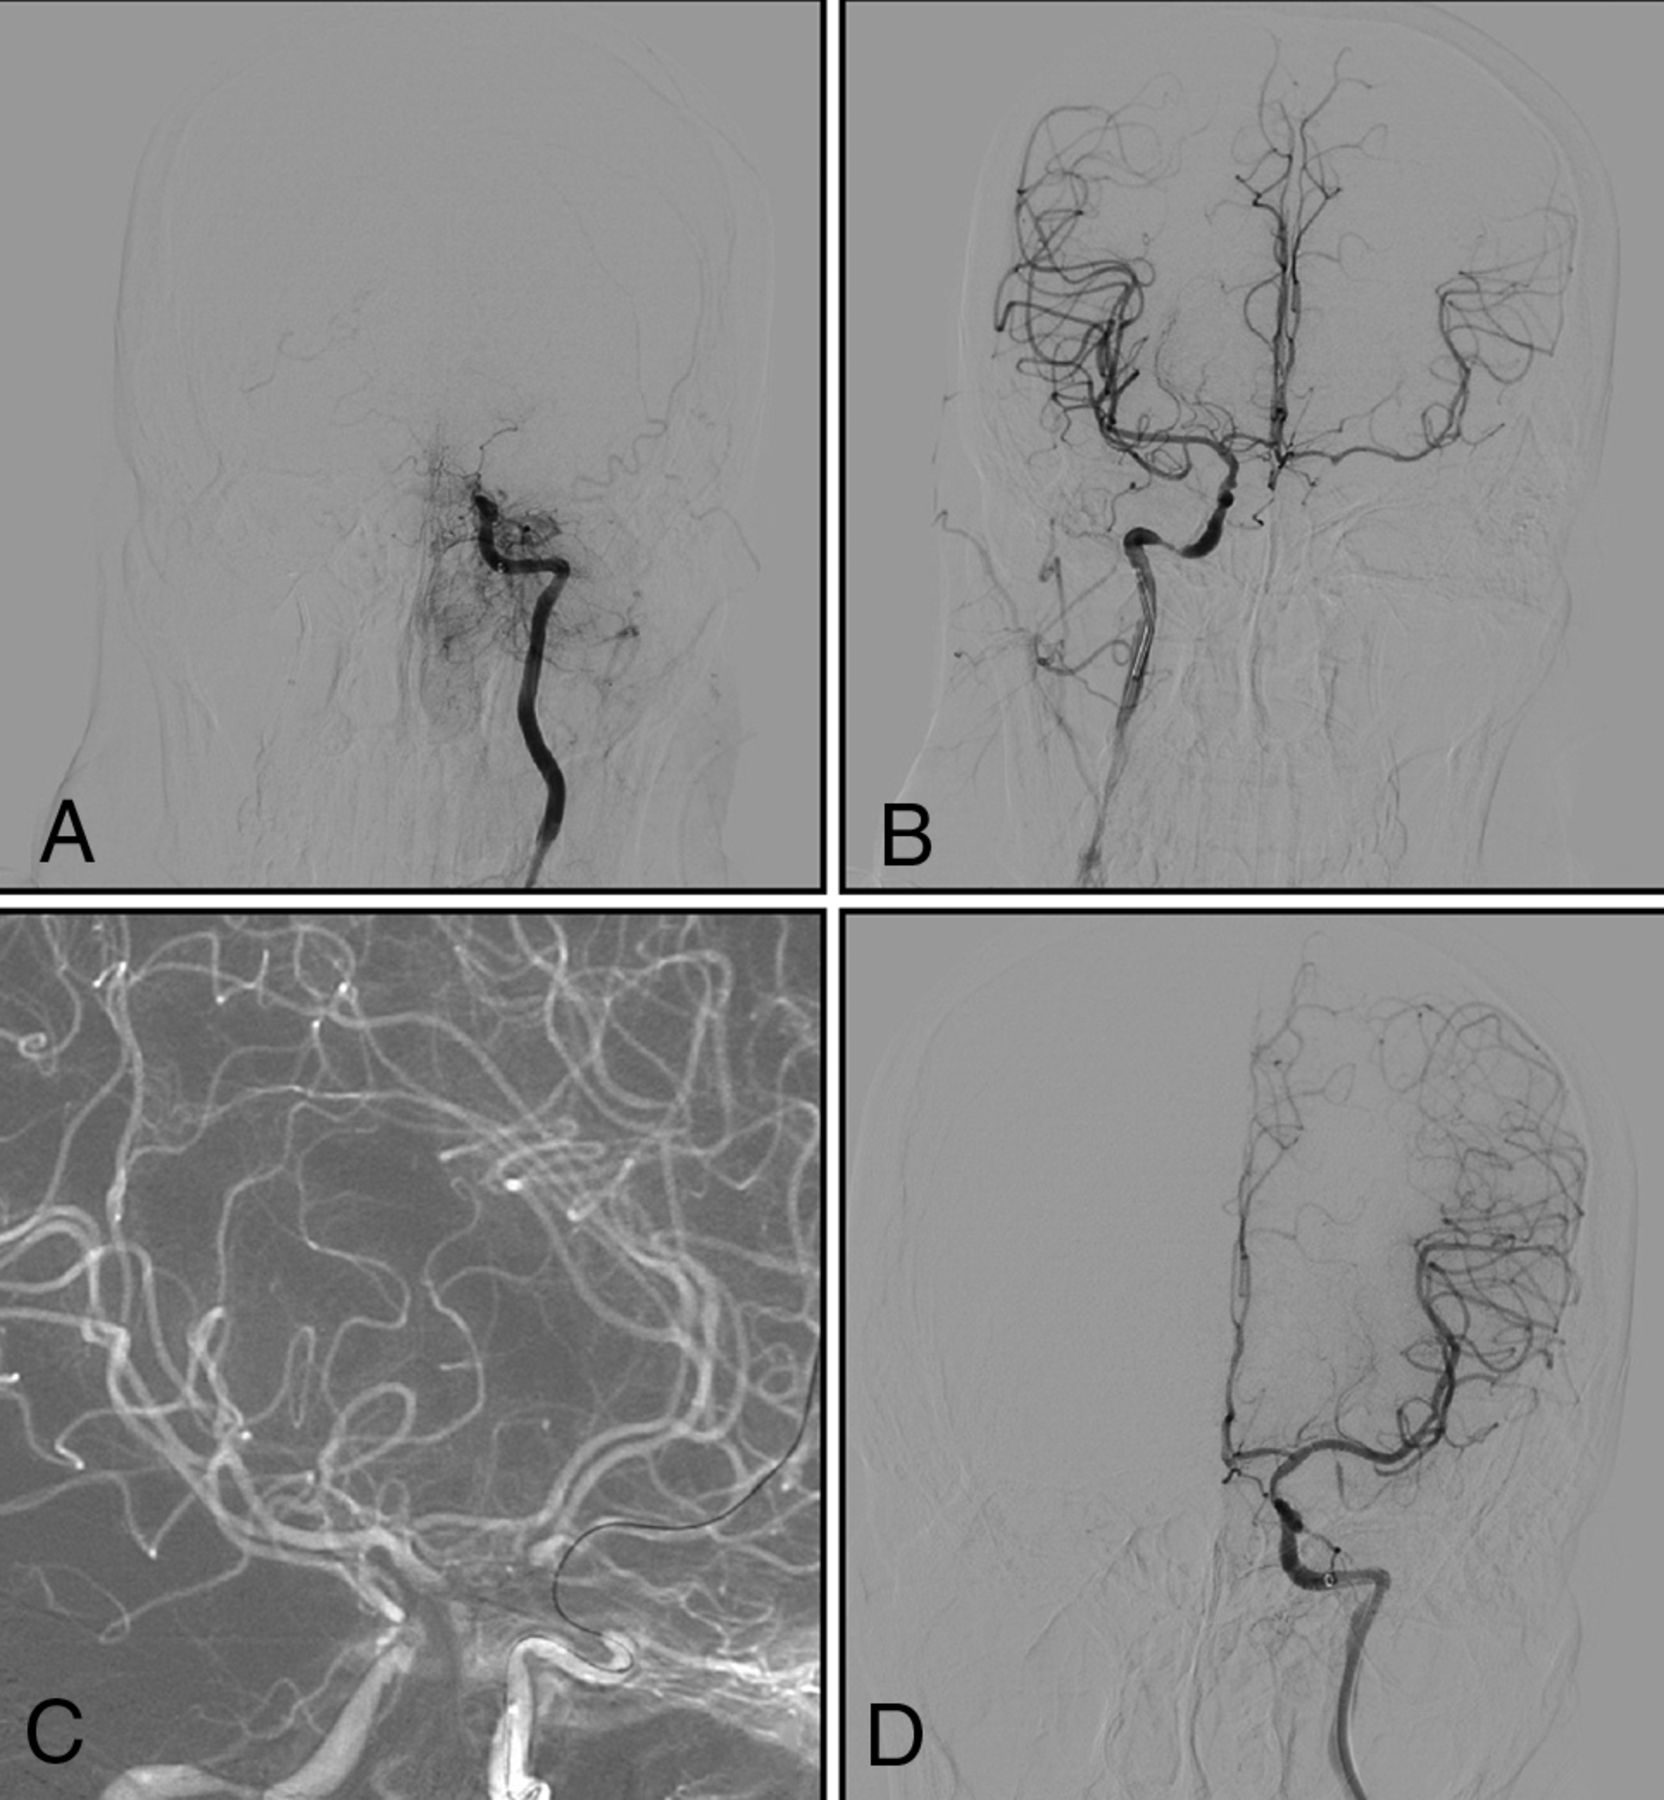

A man with right-sided weakness for 30 days, with increasingly slurred speech for 10 days. A and B, DSA shows that the left intracranial internal carotid artery is occluded, with an occlusion length of >10 mm and established collateral filling to the distal right intracranial ICA via the AcomA (type II). C, Under dual-roadmap guidance, the microwire, in combination with a microcatheter, passes through the occluded segment. D, Successful recanalization.

A man with left-sided weakness for 20 days. A and B, DSA shows that the right intracranial internal carotid artery is occluded, with uncertain occlusion length and no established collateral filling to the distal right intracranial ICA via the AcomA or PcomA (type III). C, The microwire, in combination with a microcatheter, passes through the occluded segment. D, Successful recanalization.